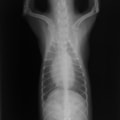

D:胸部レントゲン写真 正面像

胸部レントゲン検査において重度の心拡大と肺水腫が認められた。超音波検査では、重度の僧帽弁閉鎖不全症、三尖弁閉鎖不全症、中程度の大動脈弁閉鎖不全症を合併していることが判明した。三尖弁逆流速度から肺高血圧症が示唆された。